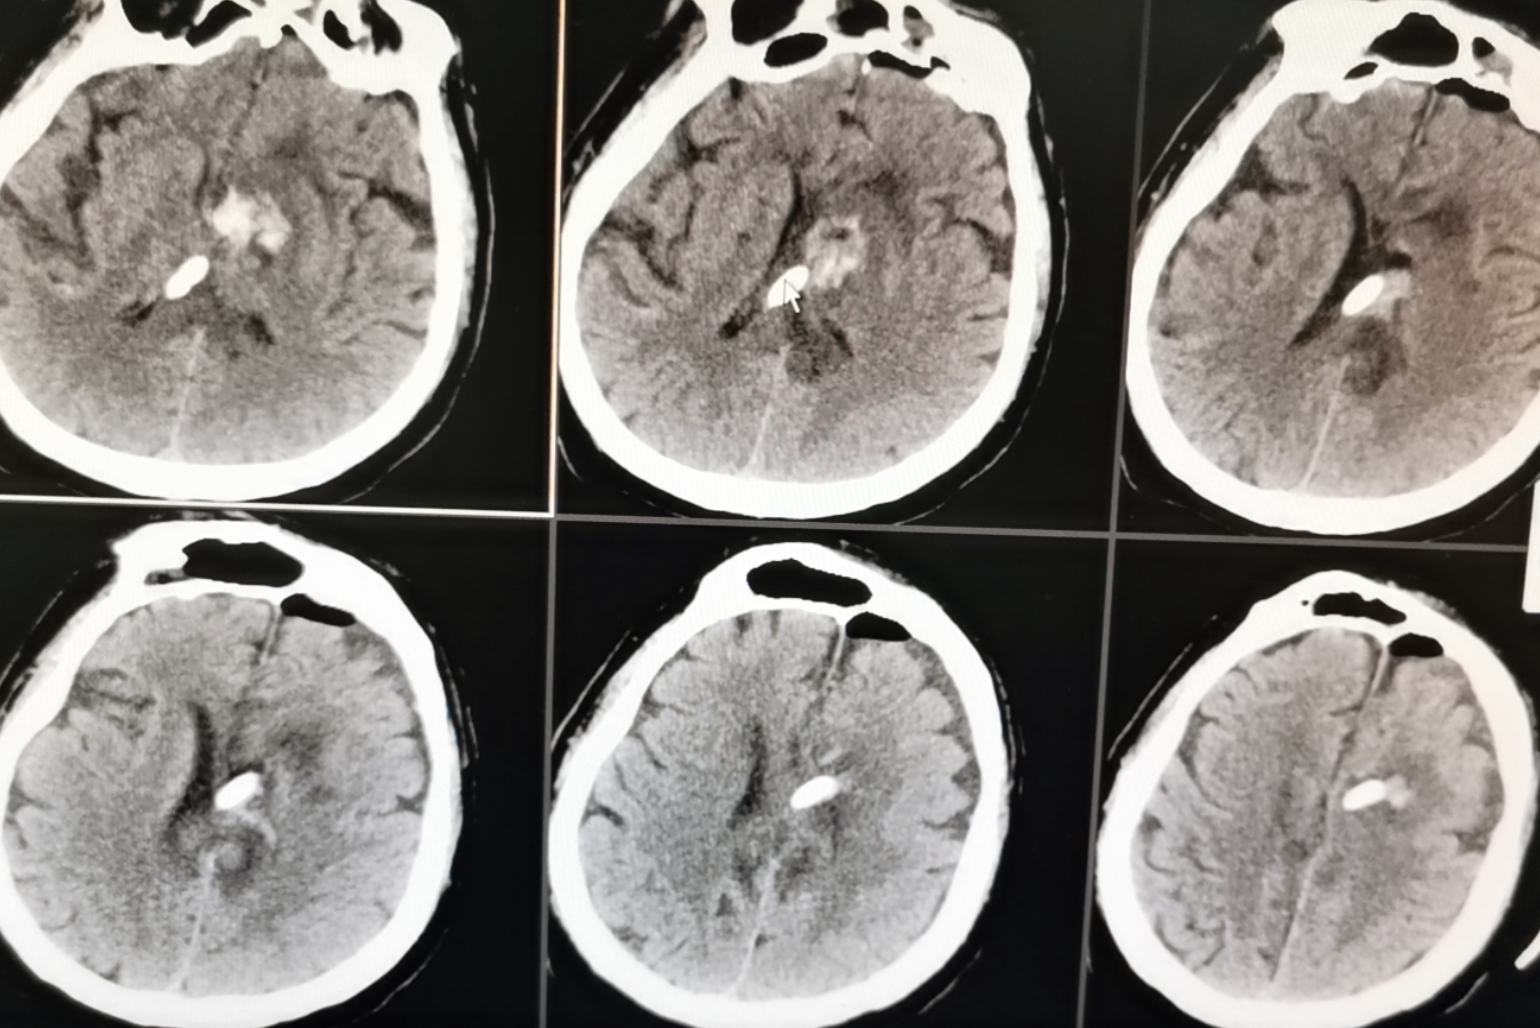

术前影像

神经内镜微创治疗高血压脑出血

术后显示血肿清除满意